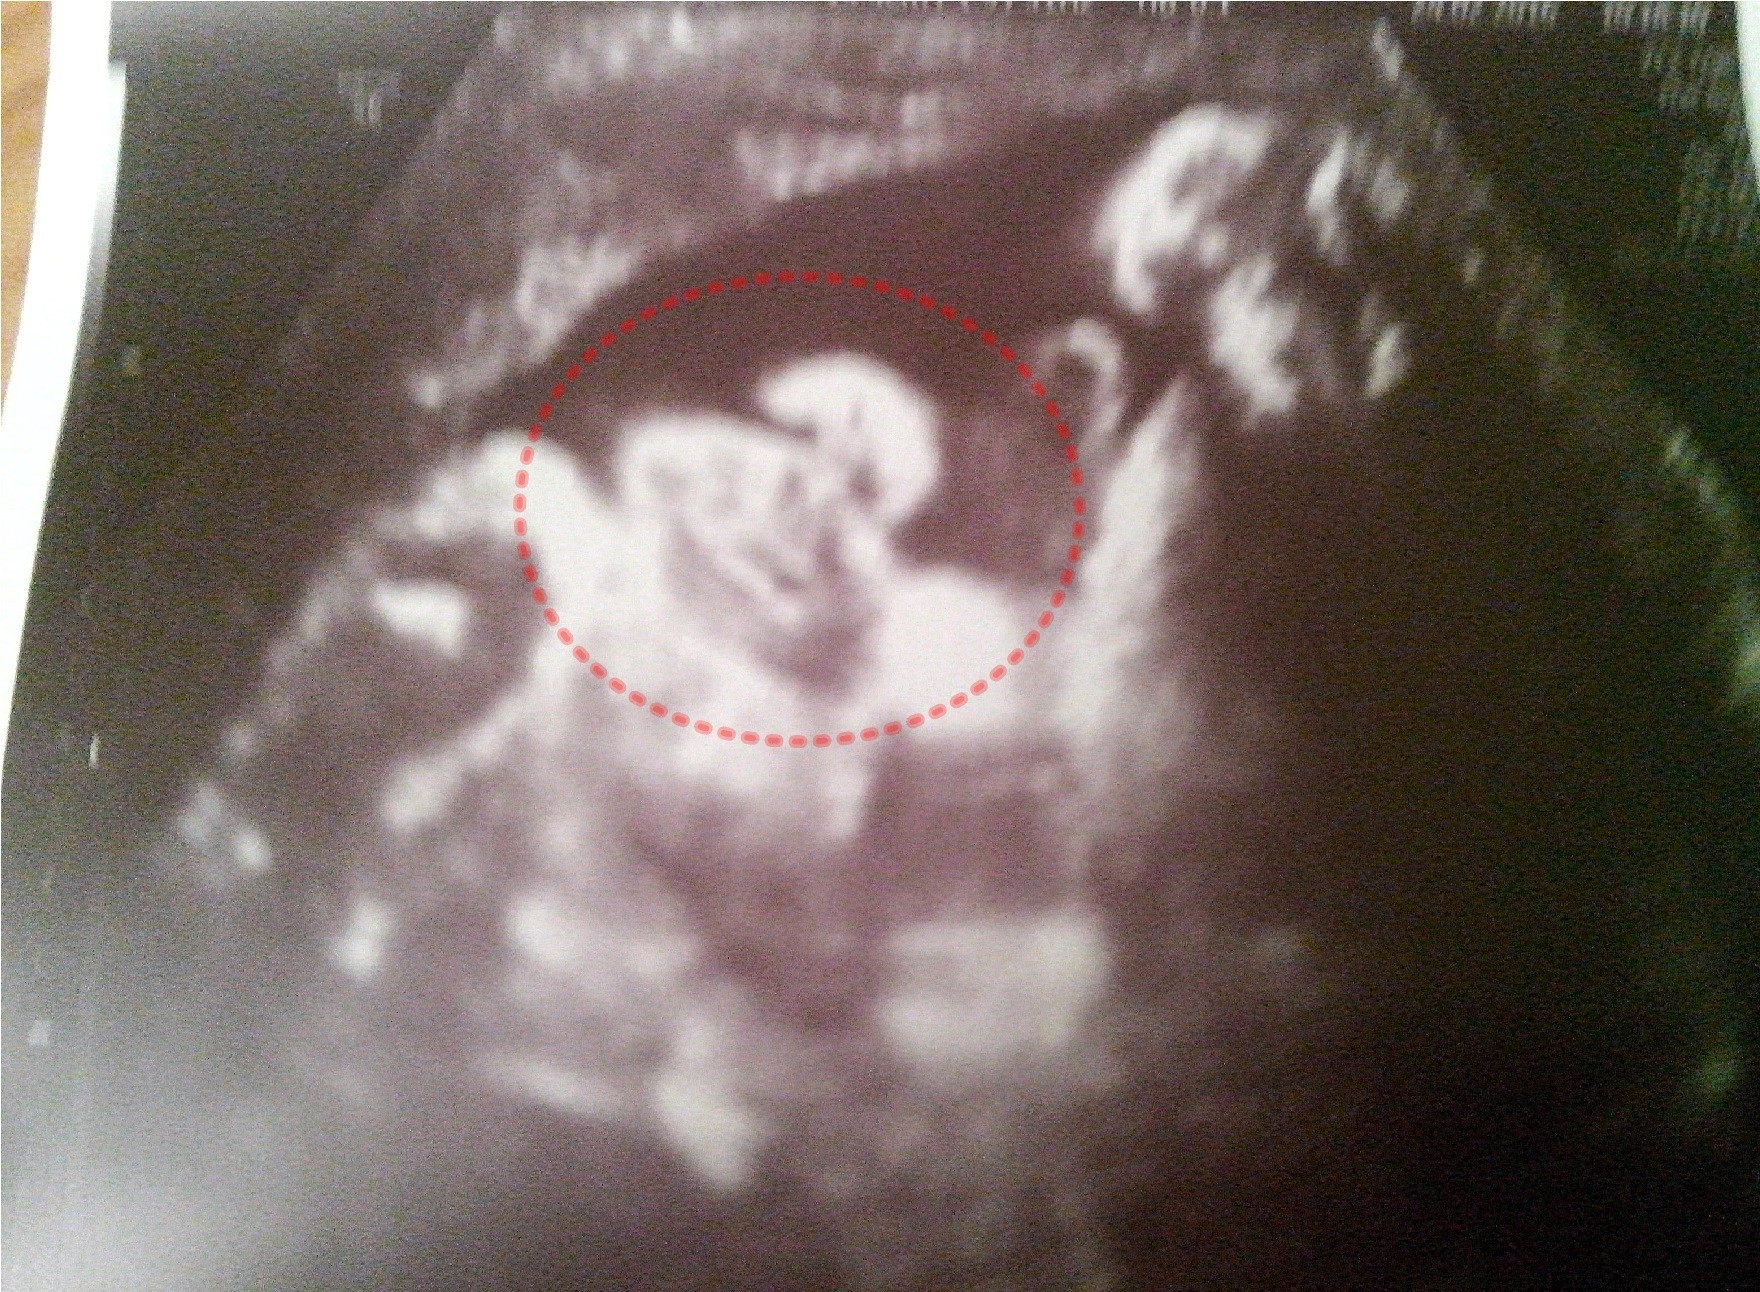

Lucinda - ja nawet nie udaje ze tam u Ciebie cos widze. Tez nigdy nie wiem na ekranie o co chodzi i na poczatku pytalam lekarz dokladnie wskazywal ze np. tu zoladek ale i tak dla mnie to magia bo wszystko tak samo wiec teraz jak pokazuje i pyta "o tytaj jest widzi pani?" To ja zawsze "tak tak widze doktorze"

a guzik tam widze